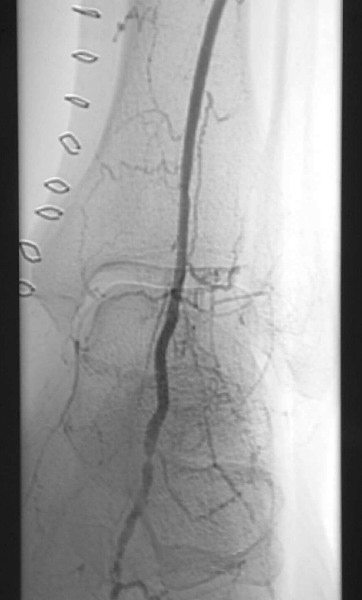

What Did The Angiogram Reveal?

An angiogram revealed extensive tibial peroneal disease on the left limb with occlusion of all vessels to the mid-calf level. There was reconstitution in the anterior tibial that provided dominant flow to the foot and reconstitution of the dorsalis pedis artery. A MRI of the left foot revealed multiple areas of small abscesses associated with the ischemic ulcers but no evidence of osteomyelitis. After the failed bypass, vascular surgeons were consulted and repeat vein mapping confirmed the absence of a usable vein conduit. With the history of aborted left lower extremity bypass, the multidisciplinary team planned for endovascular limb salvage with interventional radiology. Noninvasive vascular testing included TcPO2 of the left pretibial region (49 mmHg) and the left dorsum (30 mmHg). A diagnostic angiogram prior to the aborted surgical procedure revealed a patent abdominal aorta, iliac arteries and left superficial femoral artery. The femoral bifurcation was intact. The above- and below-the-knee popliteal artery also was patent and without stenosis. The posterior tibial artery was occluded at the level of the mid-calf. The peroneal artery was severely diseased. The anterior tibial artery had proximal, hemodynamically significant stenosis and a 30 mm long occluded segment at the level of the lower one-third of the calf. There was hemodynamically significant stenosis of the dorsalis pedis artery at and just below the level of the ankle joint.